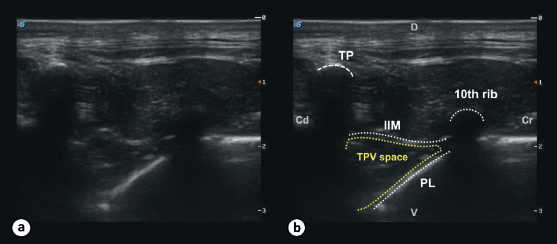

The most caudal intercostal space with visualization of pleural movement was the selected point to insert the needle and later the catheter. The last rib was identified by palpation and the transducer was positioned along its long axis. The rib was visualized as a hyperechoic line with posterior acoustic shadowing. The transducer was then moved cranially as many intercostal spaces as we needed until the movement of the PL from manual ventilation could be visualized. Once the most caudal intercostal space with visualization of pleural movement was identified, the transducer was returned to the rib at its caudal aspect. This rib was followed dorsally until the transverse process (TP) was identified. The ultrasound transducer was gradually rotated anticlockwise until the apex of the TPV space was visualized as a wedge-shaped hypoechoic region bordered by the hyperechoic line of the PL below and the internal IIM above (Fig. 1). The final orientation of the transducer prior to the injection was in an oblique sagittal plane (Fig. 2).

Fig. 1. Ultrasound image of the TPV space in a dog cadaver. The image shows the ultrasonographic appearance (a) with the landmarks for the TPV block (b). The TPV space can be visualized in between the 11th TP and the 10th rib and is delineated by the internal IIM dorsally and the PL ventrolaterally. (Cd): caudal; (Cr): cranial; (D): dorsal; (V): ventral.